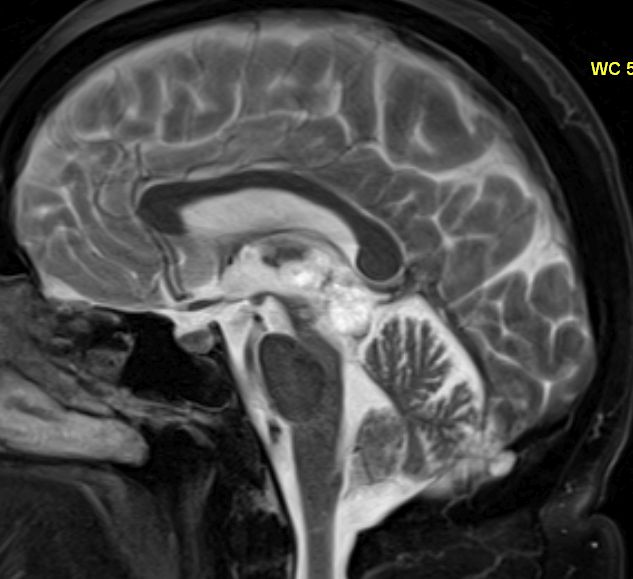

Vierhügelplatte 66-jährige Frau mit Sehstörungen, Ptose rechts mehr als links, Gehörverschlechterung und Gleichgewichtsstörungen. Stereotaktische Biopsie: Astrozytom Grad 3 (Grad unsicher).